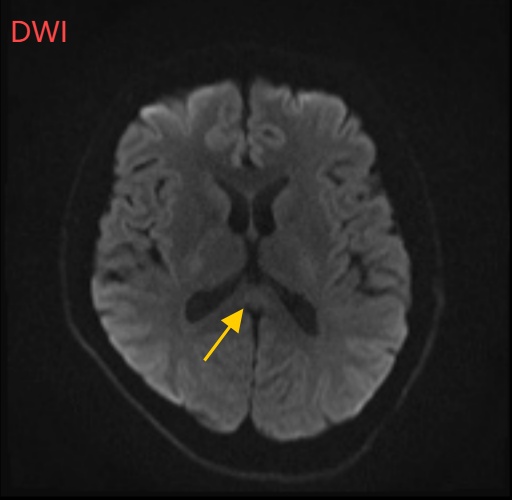

经过头部磁共振平扫、弥散、增强影像等检查

可逆性胼胝体压部综合征

小董的影像结果显示,胼胝体压部发生病变

经过一周治疗,小董的胼胝体压部病变明显好转